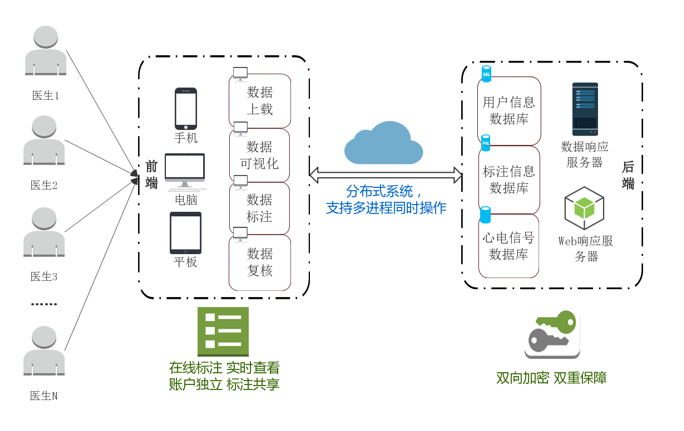

二、构建了心电图的分布式标注工具LabelECG。LabelECG 是一个在线分布式心电标注工具。医生可以通过台式机、笔记本电脑、平板电脑甚至手机上的网络浏览器访问 LabelECG。LabelECG 更易于部署和负责的数据管理性能,使医生可以忽略对数据的操作,专注于心电图的标注。LabelECG 能够帮助用户上传、可视化、注释和修改他们的心电图记录。

LabelECG:心电的分布式标注工具